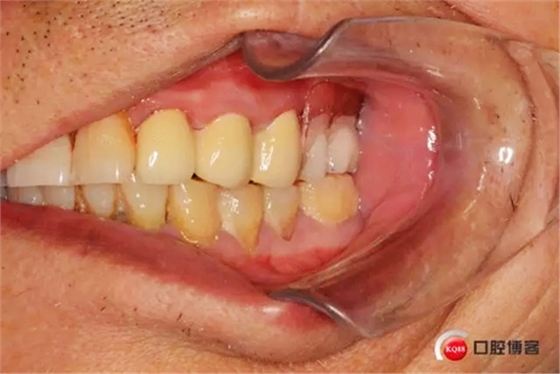

樁核帶入口腔情況

制作完成的義齒,22號(hào)牙前伸合有創(chuàng)傷調(diào)出金屬不影響美觀沒(méi)有修復(fù)

戴入口腔的合面觀,患者下頜缺失7,因單端合力問(wèn)題此牙也沒(méi)有修復(fù)7

咬合情況.